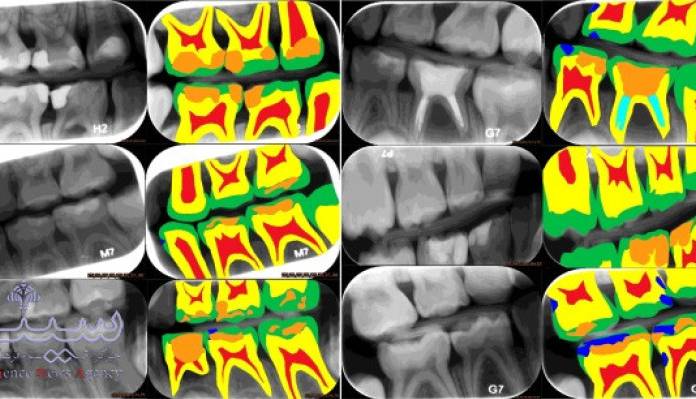

تشخیص پوسیدگی دندان با پشتیبانی هوش مصنوعی

مطالعات موفق محققان آلمانی نشان داد که استفاده از هوش مصنوعی در تشخیص پوسیدگی های [...]